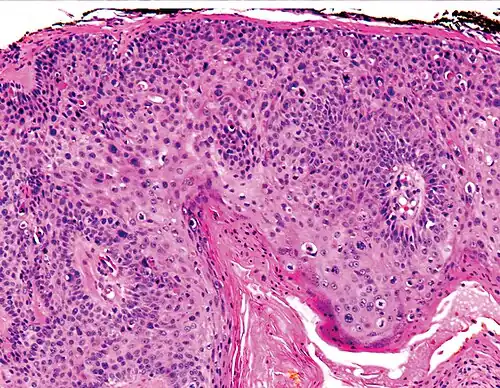

Invasive disease

In invasive cSCC, tumor cells infiltrate through the basement membrane. The infiltrate can be somewhat difficult to detect in the early stages of invasion: however, additional indicators such as full-thickness epidermal atypia and the involvement of hair follicles can be used to facilitate the diagnosis. Later stages of invasion are characterized by the formation of nests of atypical tumor cells in the dermis, often with a corresponding inflammatory infiltrate.[12]

-

Superficially invasive cutaneous squamous-cell carcinoma. These lesions often do not show the marked pleomorphism and atypical nuclei of cSCC in situ, but manifest early keratinocyte invasion of the dermis.[12] -

High magnification demonstrates the pleomorphism of the invading keratinocytes[12] -

Invasive nests with characteristic large celled centers. Ulceration (at left) is common in invasive cSCC.